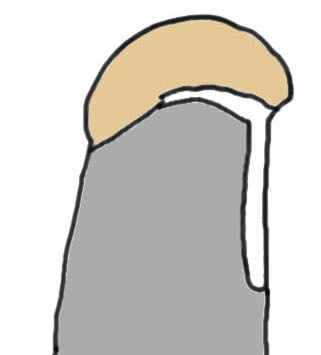

Tear patterns of supraspinatus and infraspinatus

| Crescent shaped | U shaped | L Shaped |

|---|---|---|

|

Small to medium tears Repair to footprint |

Large tears Need margin convergence then repair to footprint |

Antero-superior or postero-superior tears Need to mobilize cuff anterior or posterior |

|

|

|

Crescent, U shaped and massive rotator cuff tears